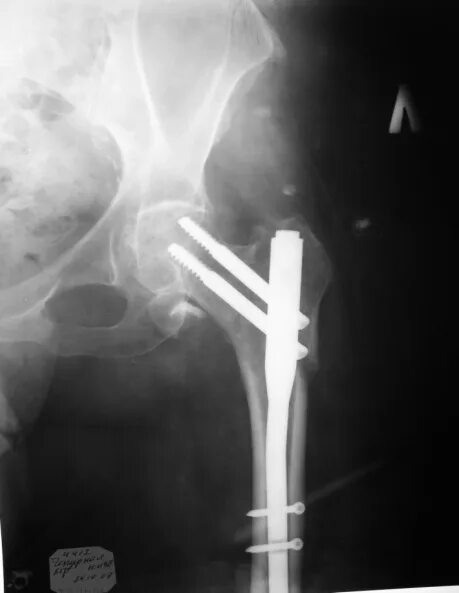

Перелом 1 3 бедра